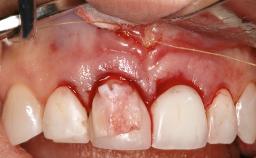

Reconstructive Treatment of a Peri-Implantitis Defect at an Implant in a Mandibular Molar Site

In this case, Mario Roccuzzo utilizes surgical bone regeneration treatment around implant 46 using a bone graft substitute and a connective tissue graft to resolve peri-implant inflammation, reduce the probing depths, and prevent further progression of disease.